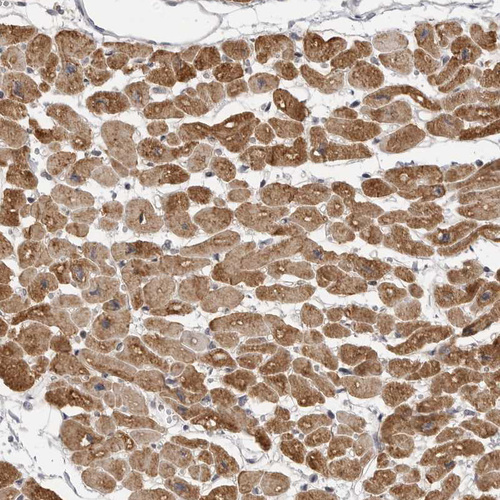

Immunohistochemical staining of human skeletal muscle shows moderate cytoplasmic positivity in myocytes.